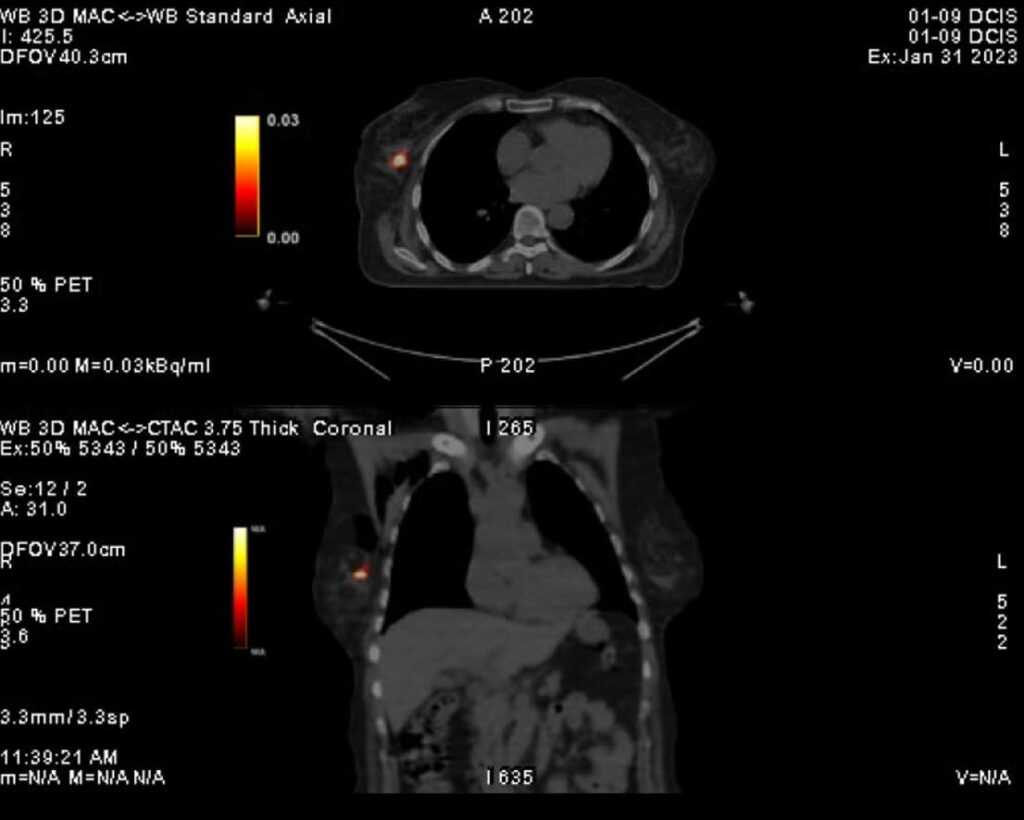

DCIS 24 hours post injection PET scan

DCIS 24 hours post injection

Human cases